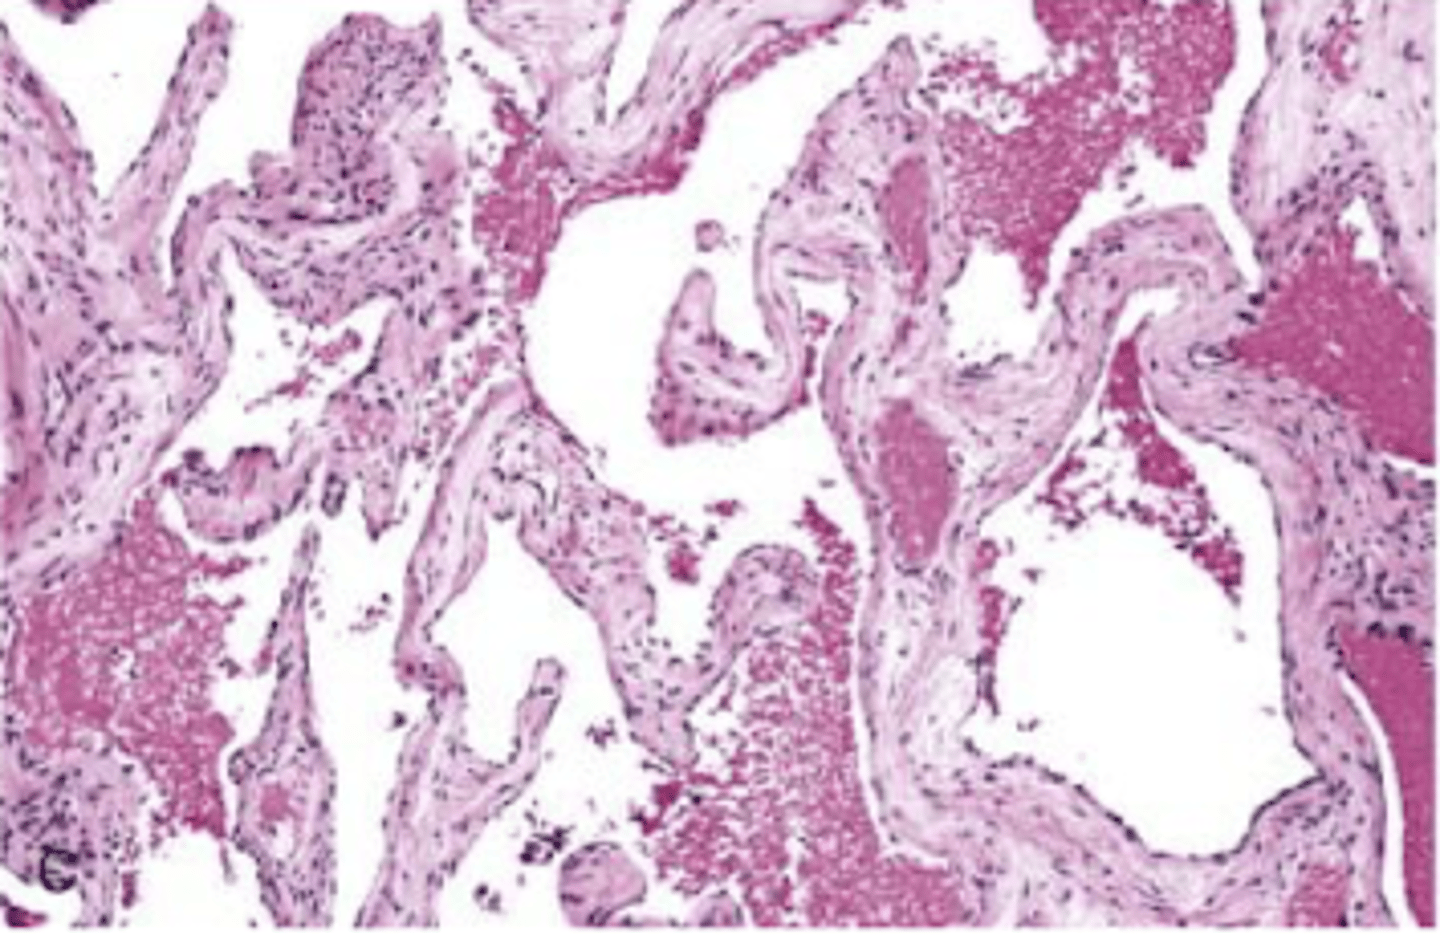

cavernous hemangioma

large blood filled dilated vascular changes with CT stroma

do not regress